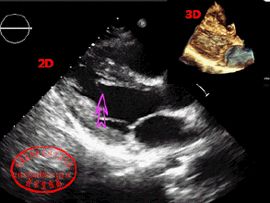

左室假腱索是從原始心臟的內肌層衍生而來,多數為緻密纖維組織,少數由心內膜包裹的心肌構成,其數目不等,既有單條,也可多條,以往僅由屍檢偶然發現,目前二維超聲心動圖已成為活體診斷左室假腱索的首選方法。幾乎一個世紀以來,一般認為左室假腱索是一種無臨床意義的解剖學變異,近年來認為左室假腱索可能與心臟雜音、心律失常和胸痛、胸悶、心悸有關。

綜上所述,假腱索雖然不是疾病,但它卻容易與某些疾病相混淆,在行心臟超聲檢查時應多切面認真觀察,以助於與這些疾病相鑑別。隨著超聲心動圖的普及套用和檢出率的提高,不再認為它是一種無臨床意義的解剖學變異,而是引起心臟雜音、心律失常和胸痛、胸悶、心悸的原因之一。對於那些心前區有雜音、心律失常和胸痛、胸悶、心悸者均應進行心臟的檢查,以判斷是否由假腱索引起的。